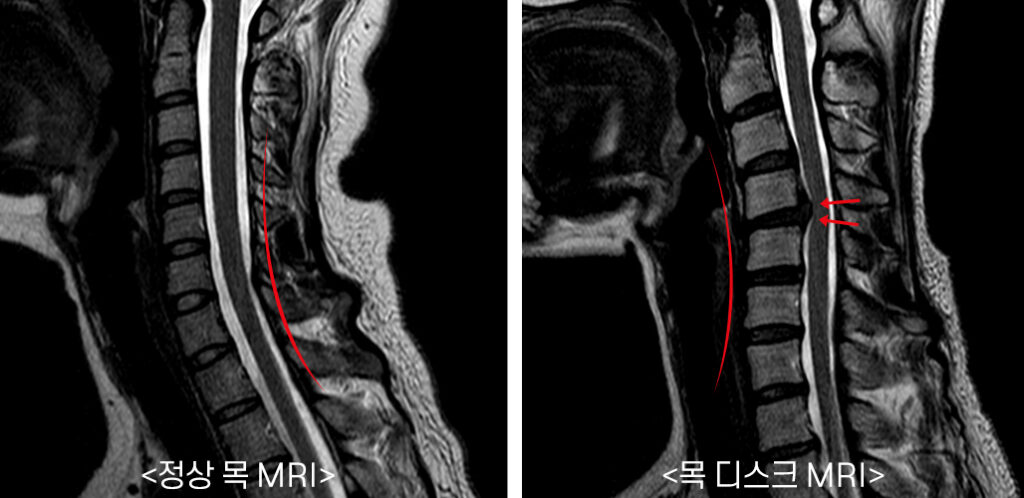

목 디스크란 경추 뼈와 뼈 사이의 추간판 ( 디스크 )이 탈출하였거나 파열돼 경추신경이 자극 또는 압박을 받아 경항부 ( 목 ), 경견부 ( 목과 어깨 ), 견배부 ( 어깨와 등 ), 상지 ( 팔 )에 통증 및 신경학적증상을 나타내는 질환 이고요. 경추는 운동성이 큰부위 이예요.

경추의 디스크는 난폭한 압력을 받으면 돌출하여 척수나 신경근을 억누르게 된다고 합니다. 대부분의 목 디스크는 난폭한 퇴행성 전환 향후에 발생하기 때문에 많은 환자들이 만성적인 경항통 ( 목의 통증 )에 대한 오래전력을 갖고 있다고 한다면가 대다수 이고요. 그럼 이제부터 적극적으로 목 디스크에 좋은 운동을 따져보도록 하겠습니다.